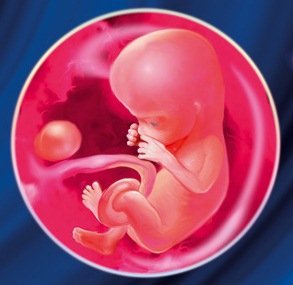

На этой неделе ваш малыш принимает очертания настоящего крошечного человека. Даже хвостик, который был у него на предыдущих неделях, уже практически исчез. Прорисовываются новые черты лица, оформляются нос и веки. В размерах голова малыша пока опережает его тело. На ножках теперь можно различить пальчики. Формируются и внутренние органы, в том числе пищеварительный тракт (кишечник) и половые органы (яички или яичники). На девятой неделе беременности у ребенка уже могут сформироваться отдельные мышцы, поэтому он может начать шевелиться. Однако эти шевеления вы почувствуете только во втором триместре. Хотите узнать больше о том, что происходит во время беременности? Скачайте наш гид по беременности. В нем вы найдете полезную информацию о ведении беременности, питании, наборе веса и пр.

Во-первых, ваш будущий малыш подрос, достиг отметки в 2-3 см и стал весить целых 4 г, и главное, это только начало. Во-вторых, его мозг продолжает активно развиваться, он разделился на два полушария, которые густо покрыты первыми извилинами. Формируется мозжечок, который координирует движения ребёнка, в частности управляет ими во время плавания. А усовершенствование нервной системы помогает появлению первых рефлексов малыша, таких как глотательный и сосательный.

Конечности малыша продолжают развиваться, они становятся длиннее и толще. Пальчики на руках уже не имеют перепонок, но между пальчиками ног они ещё присутствуют. Ладони рук приобретают привычные очертания. Если посмотреть на личико, то можно увидеть, что уже сформировались губы. Во рту начинают закладываться молочные зубы.

Все основные органы вашего ребенка на месте (NHS 2018) к 9 неделе, хотя в ближайшие месяцы им предстоит много тонкой настройки. К настоящему времени их сердце закончило делиться на четыре камеры (Moore et al 2019a, Visembryo nda), а их нос и обоняние развиваются (Hill 2019a, Moore et al 2019b, Visembryo nda).

Органы, мышцы и нервы вашего ребенка включаются в работу.Эмбриональный хвост вашего ребенка почти исчез (Mukhopadhyay et al 2012), и он начинает выглядеть немного более человечным.К концу этой недели они будут иметь длину около 2,3 см (0,9 дюйма) и вес около 2 г (0,07 унции) (Hill 2019b). Это примерно размер виноградины.

Сейчас ваш ребенок должен быть размером с виноградину или оливку, скажем, длиной в один дюйм.

Малыш весит всего 2 грамма!